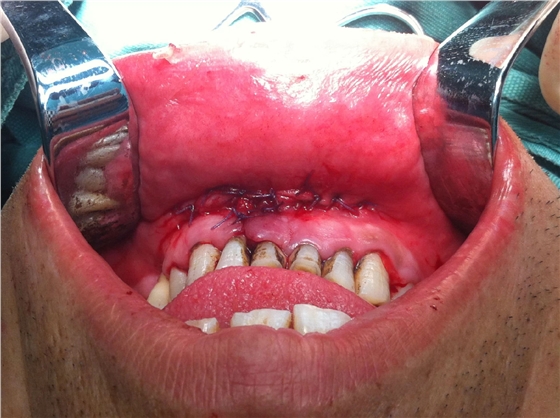

以上為術中所拔出患牙及剝離的頜骨囊腫。